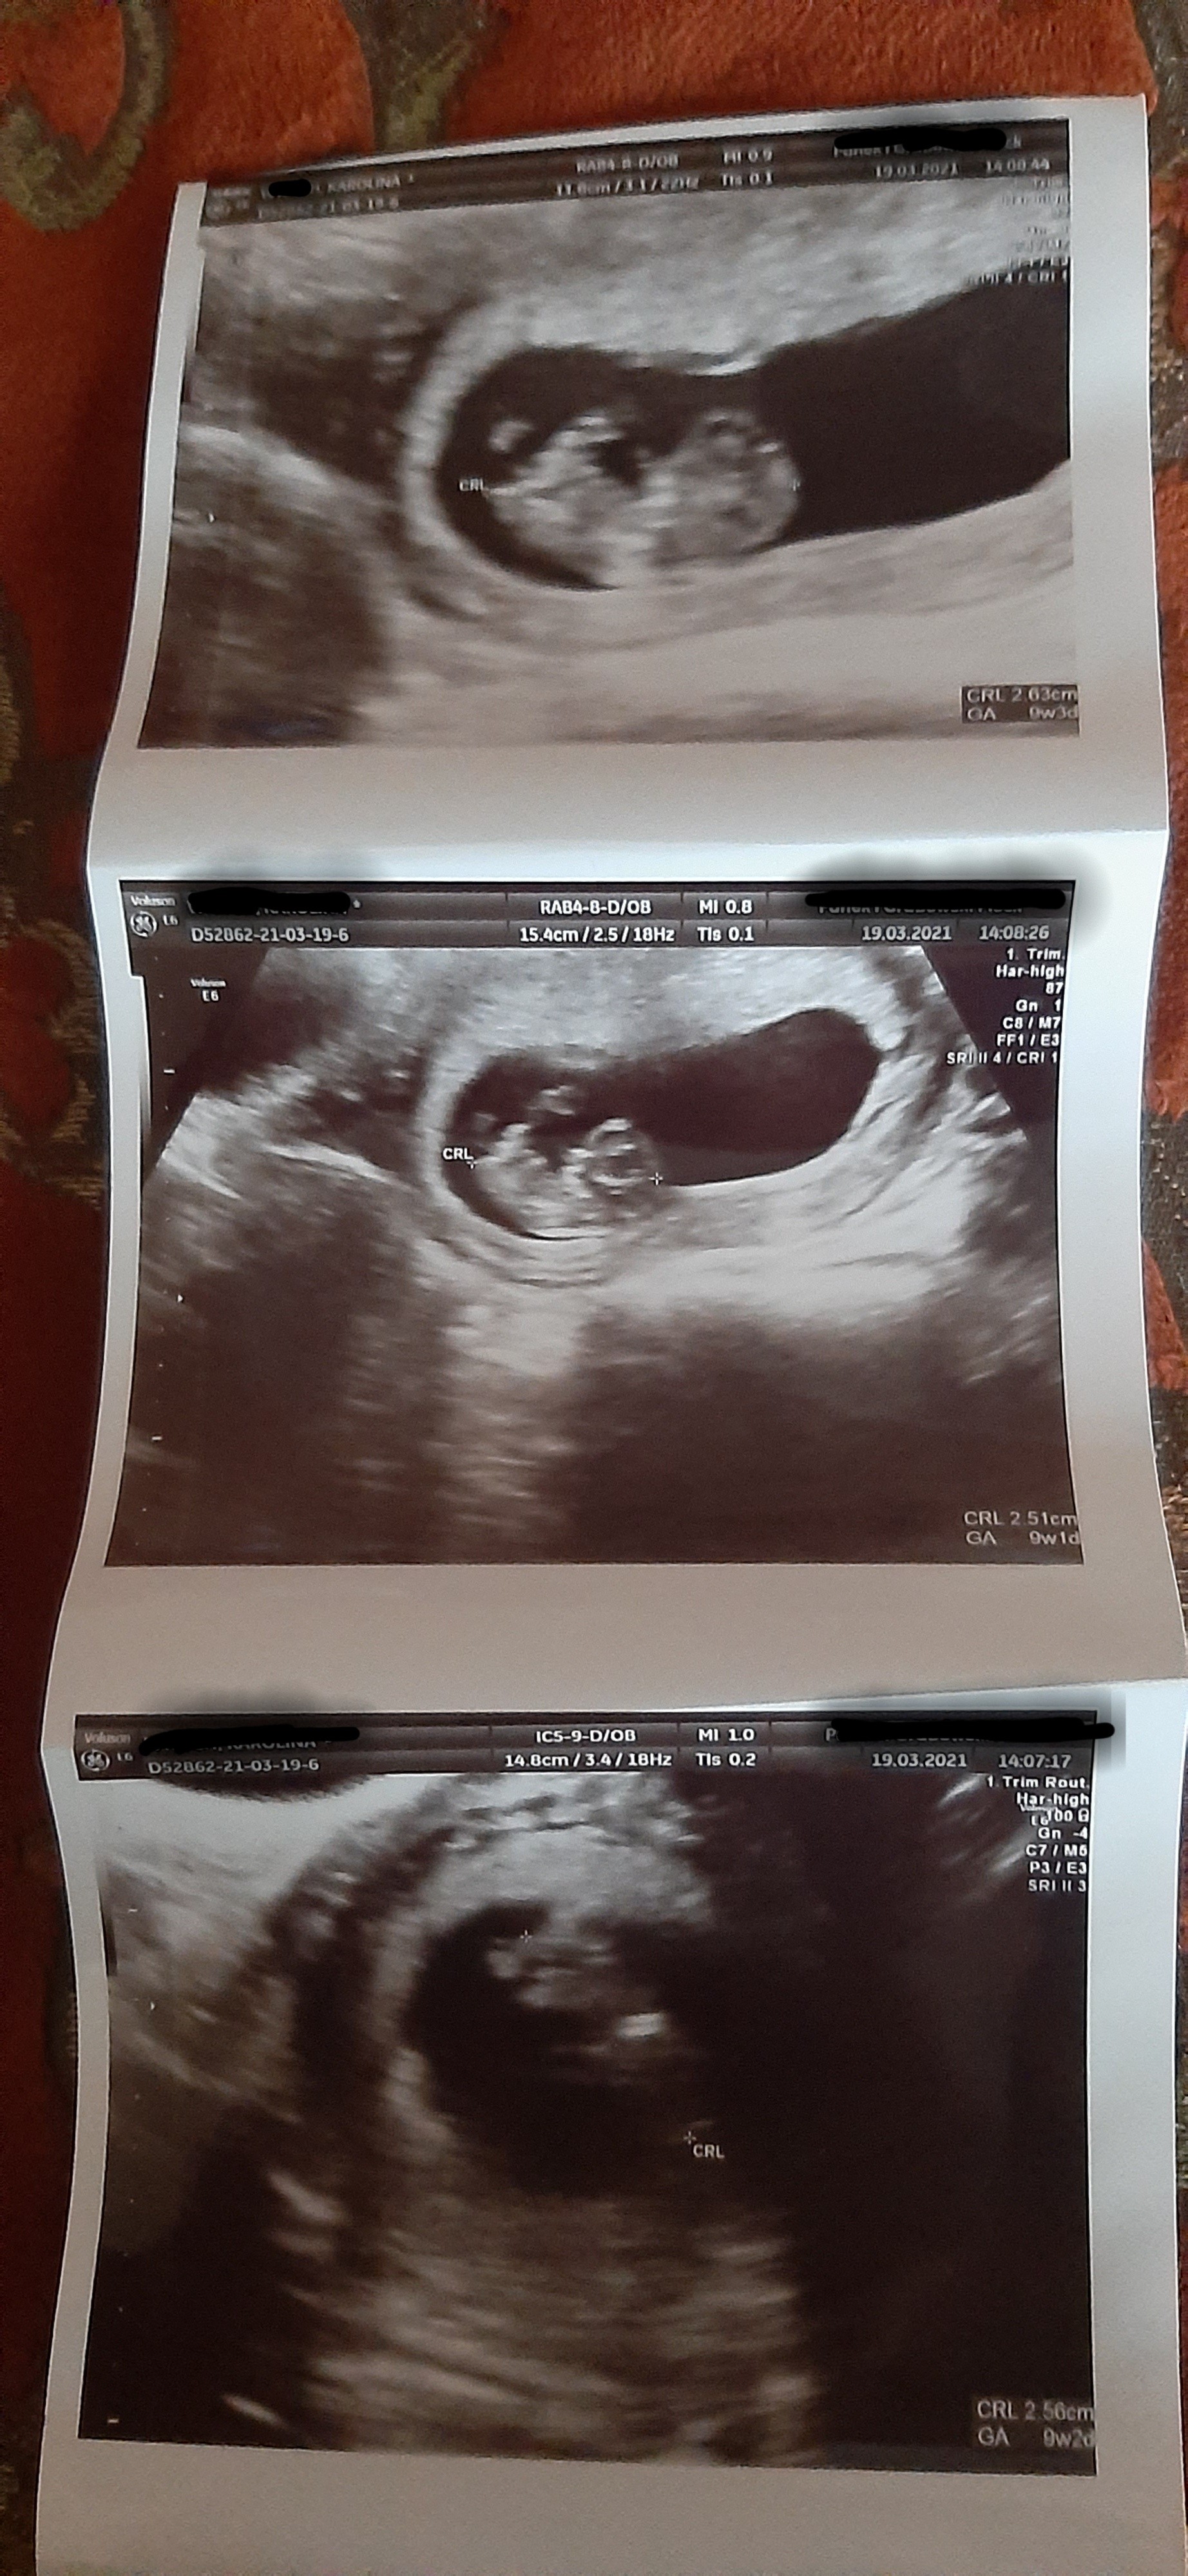

Ja byłam wczoraj na wizycie, 9+2 dzidzia rośnie ma się dobrze, nawet chwilkę się ruszała 😍 zdjęcie nie jest zbyt wyraźne. Dziś zapisałam się na prenatalne będzie 12+6 już się nie mogę doczekać 🥰 ale to dopiero po świętach 🙈 jedyny minus ze nie wejdę z mężem :( a zawsze nam się marzyło..

• image.jpg

image.jpg

1 MB · Wyświetleń: 80